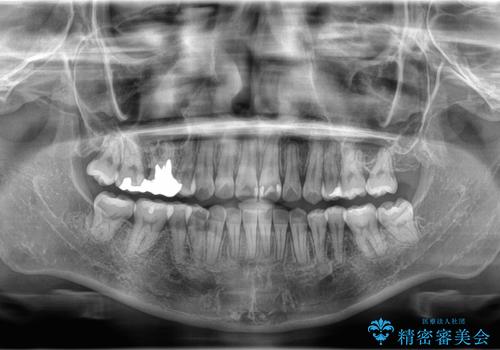

ワイヤー矯正を用いて、欠損部の閉鎖を目的とした後方からの歯の挺出・移動を行いました。

特に、親知らずを活用し、奥歯の噛み合わせを構築することに重点を置きました。

最終的には予定通りインプラントを使用せずに欠損部を閉鎖し、咬合も安定させることができました。